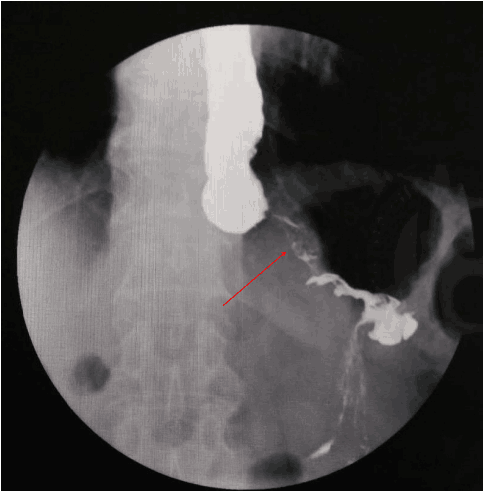

术前上消化道钡餐造影检查

(箭头所指部位明显狭窄,钡剂不能顺利通过)